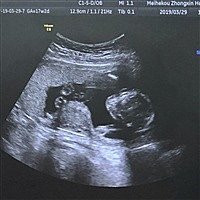

孕25周+2天